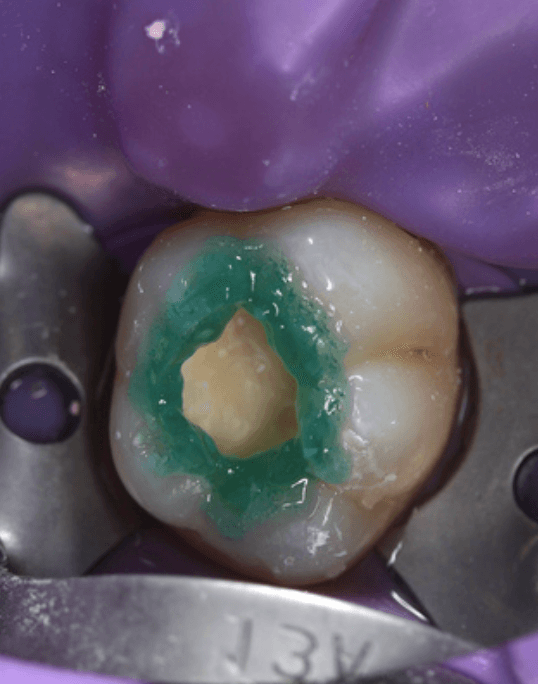

Starting the process

Dr Deesha